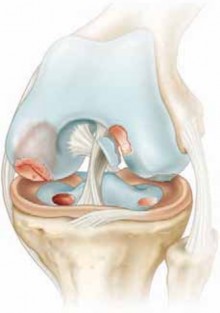

Chapter 33 Arthroscopic Meniscectomy Frederick M. Azar DEFINITION Irreparable meniscal tears are those for wh…

Posterior Cruciate Ligament Repair Chapter 44 Posterior Cruciate Ligament Repair Craig S. Mauro, Anthony M. B…

Management of Posterolateral Corner Injuries Chapter 46 Management of Posterolateral Corner Injuries Richard …